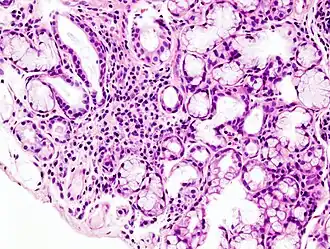

Гистологическая картина локальной лимфоидной инфильтрации малой слюнной железы при синдроме Шёгрена. Биопсия губы. Окраска гематоксилин-эозином

6. Биопсия малых слюнных желёз. Обнаруживается инфильтрация слюнных желез лимфоцитами.